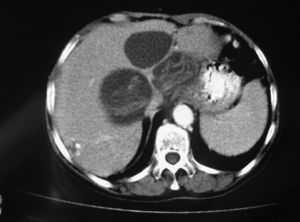

Mujer de 78 años con antecedentes de hidatidosis hepática múltiple, intervenida en por este motivo en dos ocasiones. Acude a urgencias por un cuadro agudo de dolor abdominal y náuseas de 4h de evolución. A la exploración presentaba importante afectación del estado general, con dolor difuso a la palpación abdominal y signos de peritonismo. Apirética y con constantes vitales mantenidas. En ningún momento presentó signos o síntomas compatibles con reacción anafiláctica. En las pruebas complementarias destacaba una ligera leucocitosis con fórmula y recuento celular normales. Los parámetros bioquímicos mostraron un aumento de GGT; las demás enzimas hepáticas eran normales. Se practicó ecografía y tomografía computarizada abdominal (fig. 1), que confirmaron 4 quiste hepáticos, 2 en el lóbulo hepático derecho, de 8,5 y 8cm, respectivamente, y otros 2 en el lóbulo hepático izquierdo, de 6,6 y 4,2cm, con evidencia de líquido libre intraperitoneal de 2cm de espesor. Con el diagnóstico de abdomen agudo secundario a rotura espontánea de quiste hidatídico, se realizó laparotomía de urgencia. En el acto quirúrgico se confirmó la peritonitis generalizada secundaria a la rotura de uno de los quistes, por lo que se realizó su quistectomía parcial junto con lavado peritoneal. Los estudios microbiológicos del líquido peritoneal confirmaron escólex de Echinococcus por lo que se inició tratamiento con albendazol oral durante el postoperatorio. La evolución de la paciente fue tórpida, con múltiples complicaciones durante su estancia en reanimación: sepsis de origen abdominal, síndrome de distress respiratorio del adulto, por lo que precisó soporte ventilatorio de manera prolongada, e infección de la herida quirúrgica. Al alta completó 3 ciclos de tratamiento con albendazol. En las técnicas de imagen practicadas de control a los 3 meses se observó la persistencia de las lesiones quísticas.